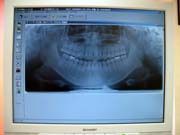

<デジタルレントゲン>

当院のデジタルレントゲンは、従来型と比べ、被曝量が10分の1と大幅に軽減されており、患者様の身体に優しいものとなっております。

又、現像までの時間も大幅に短縮され、お待ち頂く時間も短縮できます。

さらに現像の際に廃液が出ませんので、環境にも優しいものとなっております。

<デジタルレントゲンの画像>

チェアにお座りいただきながら、鮮明なレントゲン画像をご覧頂けます。